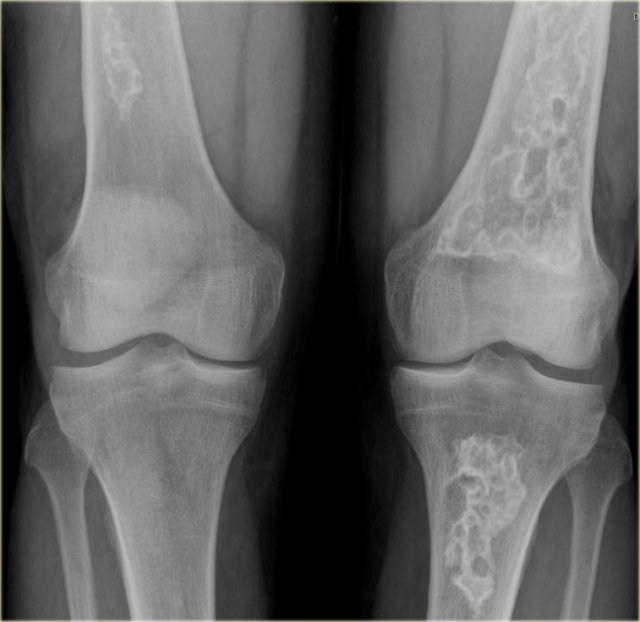

Multiple bone infarcts Multiple bone infarcts

The radiograph shows typical bone infarcts in diaphysis and metaphysis of femur and tibia..

On MR imaging bone infarcts are characterized by irregulair serpentiginous margins with low signal intensity on both T1 and T2 WI and with intermediate to high fat signal in the center part.

Enhancement after i.v. Gadolinium is usually minimal or absent (see right image).

At the periphery of the infarct a zone of relative high signal intensity on T2WI may be found.

Differentiating a bone infarct from an enchondroma or low-grade chondrosarcoma on plain films can be difficult or even impossible.

Cartilaginous tumors in particular chondrosarcoma may show endosteal scalloping, while a bone infarct does not.